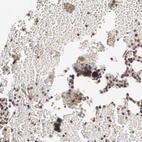

Immunohistochemistry analysis in human bone marrow and liver tissues using Anti-MXD1 antibody. Corresponding MXD1 RNA-seq data are presented for the same tissues.